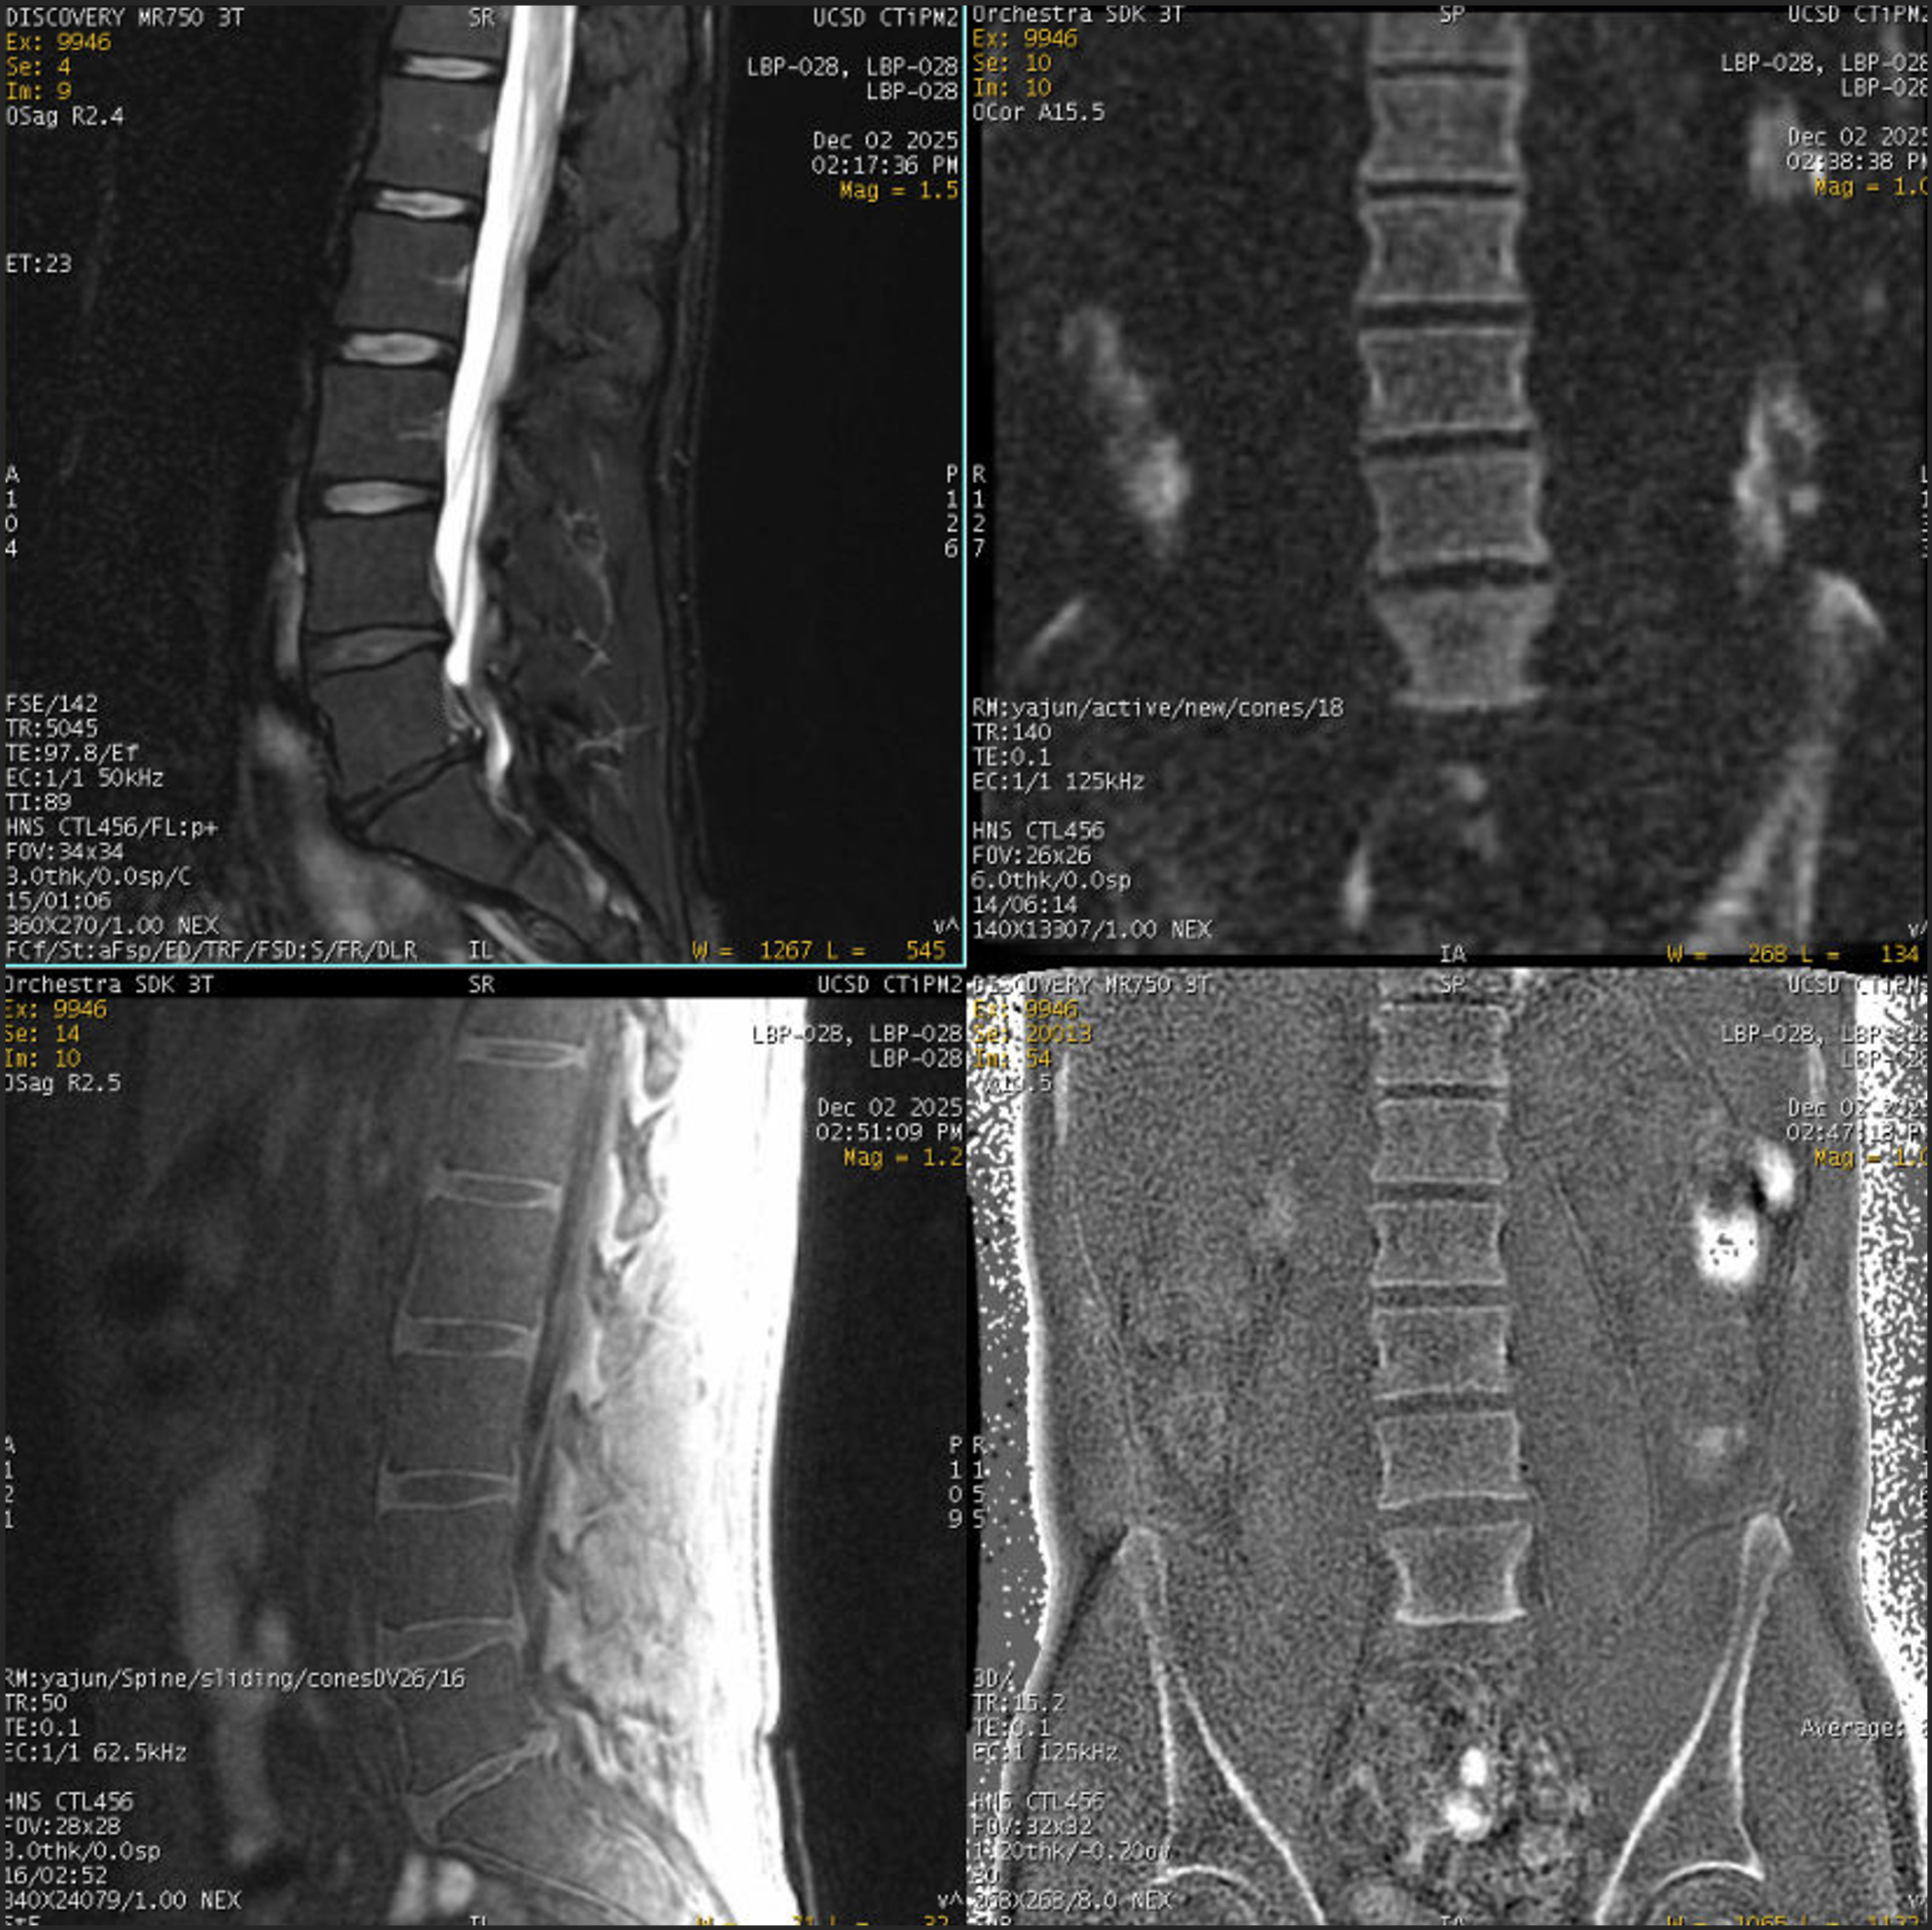

Example MR Images

../_images/ma_spine_dev_1.png